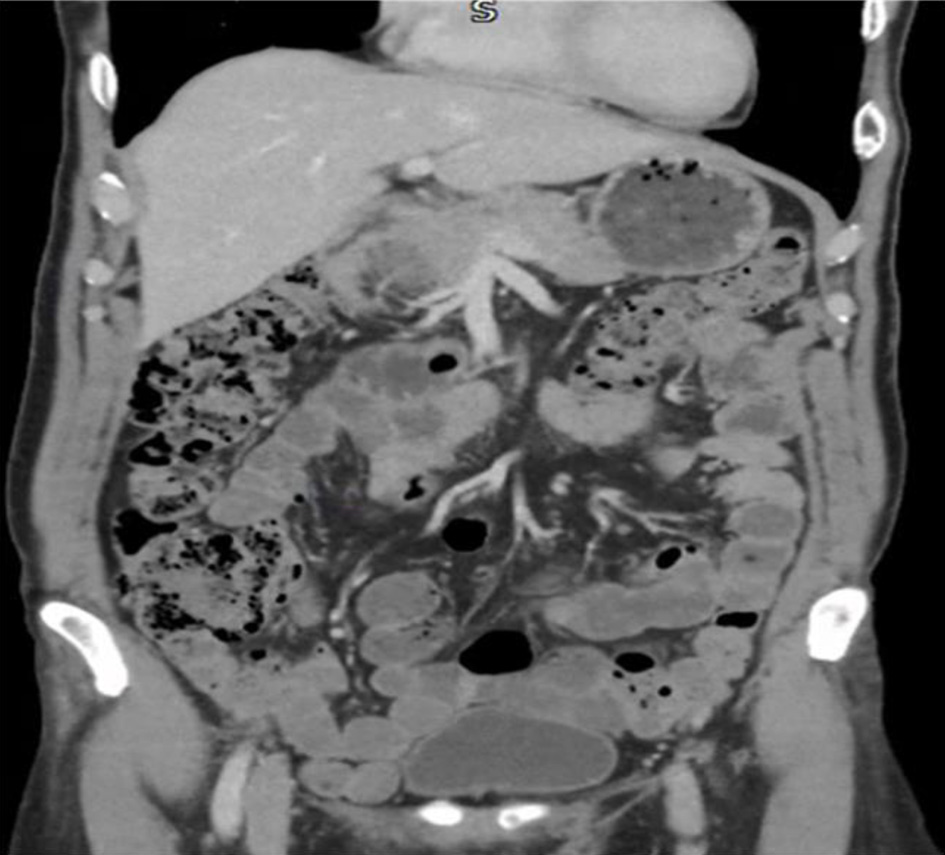

A 59-year-old Iranian male presented to his general practitioner (GP) with per-rectal bleeding and change in bowel habits. Blood investigation ordered by the GP showed no evidence of anemia but had a low white blood cell (WBC), red blood cell (RBC), and hematocrit. Table 1 displays the blood investigation results at the time of his initial presentation. He was subsequently referred via the 2-week wait pathway for colonoscopy. The colonoscopy revealed two polyps in the colon as well as a well circumscribed 15 mm erythematous patch in the rectum as shown in Figure 1. The polyps were removed, and the patch was biopsied at the time of colonoscopy. Pathology reported the polyps to be tubular adenomas with low grade dysplasia. The report also revealed the erythematous patch to consist of fragments of gastric fundic-type mucosa. Figure 1 displays the GHT found in the rectum. None of the biopsies showed evidence of dysplasia or malignancy. He also underwent an esophagogastroduodenoscopy (EGD) and computed tomography of the chest, abdomen, and pelvis (CT CAP) which were unremarkable as seen in Figure 2.

Figure 1. Colonoscopy showing gastric heterotopia identified in the rectum with traditional white light endoscopy (left) as well as narrow band imaging (right). The heterotopia is a 15-mm well circumscribed erythematous patch.